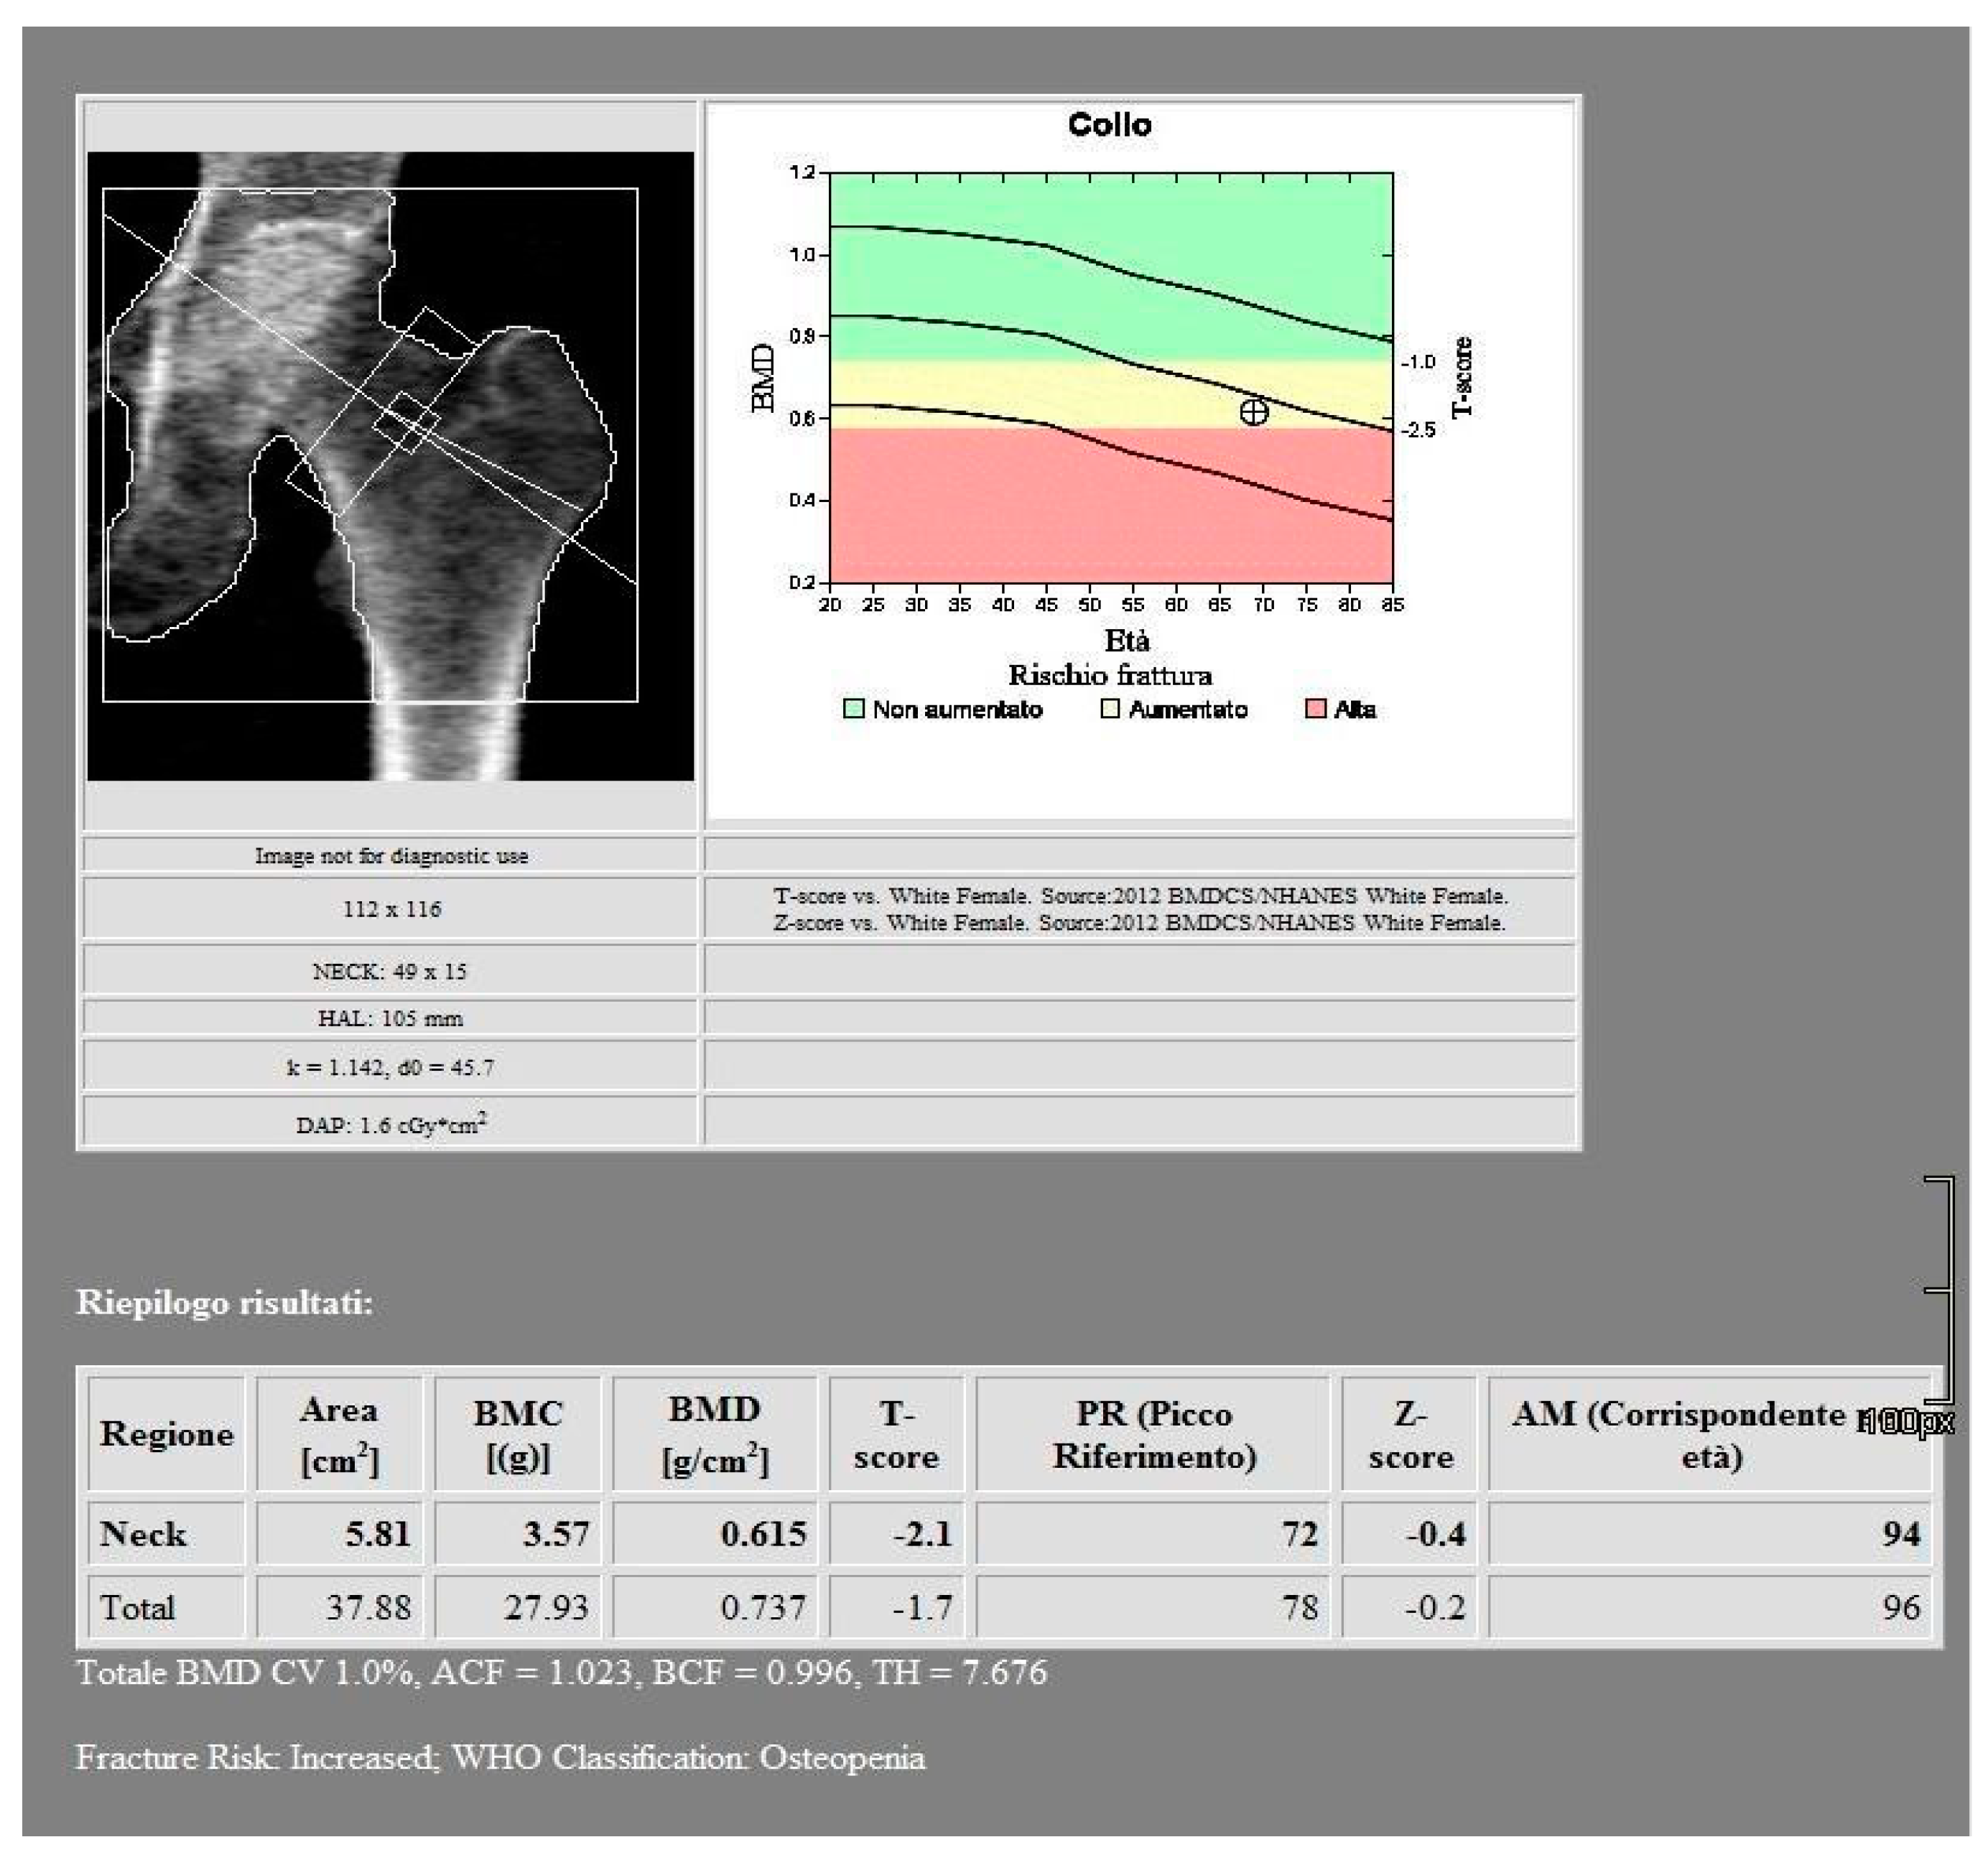

All images were acquired using a 256-slice multidetector CT system with spectral imaging capability (Revolution, GE Healthcare, Chicago, USA) using a 1.0 mm slice thickness, tube voltage of 80-140 kVp, and tube current of 200 mA (Dose Right automatic exposure control system). The CT data were reconstructed with GSI data, and MPR reconstructions were performed in coronal and sagittal planes. DXA scans were performed using a bone densitometer (Discovery A, HOLOGIC, USA) for the lumbar vertebrae (L1 to L4) and femoral neck (Figure 1 and Figure 2).

Figure 2. DXA measurements on the femoral neck.

The baseline characteristics of the 51 patients participating in the study are presented in Table 1 and Table 2. According to the BMD measurement on DXA, 15 participants were diagnosed in osteoporotic range in the lumbar area and 15 participants in the hip area. 27 participants were identified in the osteopenic range in the lumbar area and 24 participants in the hip area. 9 subjects were classified in the normal range in the lumbar area and 12 subjects in the hip area.

For the femoral neck the mean BMD and T-score on DXA images were 0.522 g/cm2 and -2.92 for the osteoporosis group, 1.19 g/cm2 and -1.7 for the osteopenic group and 1.98 g/cm2 and -0.68 for the normal group, respectively (Figure 7). There was a significant difference among the osteoporosis, osteopenic and normal groups in BMD and T-score (all p < 0.001). The mean HAP value on DECT images was 74.71 mg/cm3 for the osteoporosis group, 107.57 mg/cm3 for the osteopenic group and 121.93 mg/cm3 for the normal group (p < 0.001) (Table 2). Bland-Altman analysis revealed a bias of 0.11, with 95% limits of agreement from −1.2 to 1.4 (p = 0.2) (Figure 8).